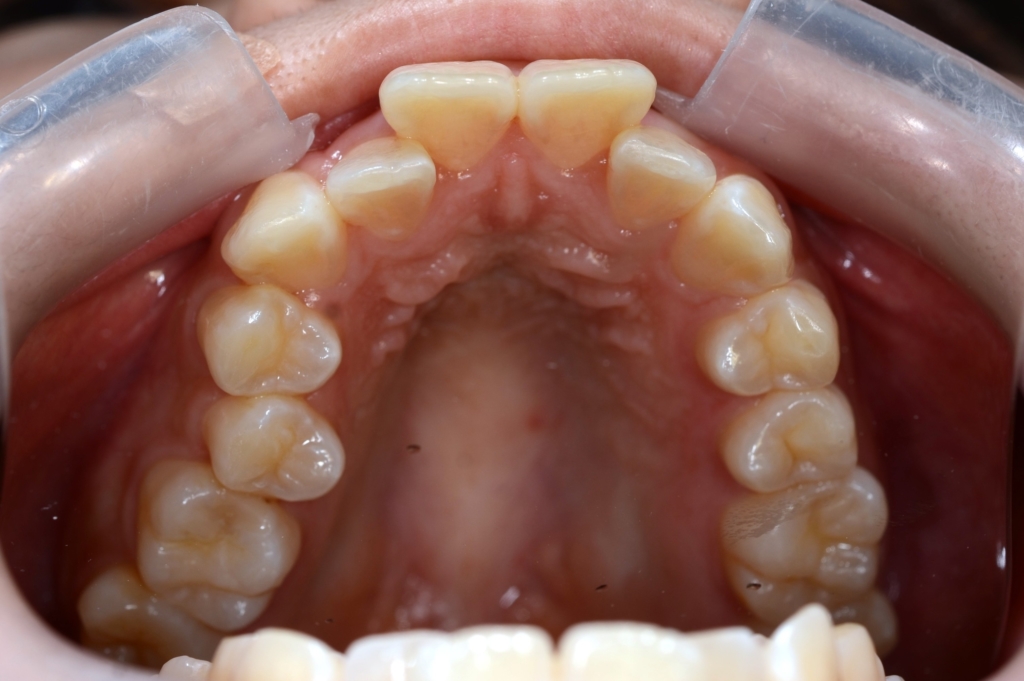

【Before】

レントゲン写真で確認すると、

この患者さんの場合、

#1.顎と歯の不調和による叢生

#2.上顎前突(出っ歯)